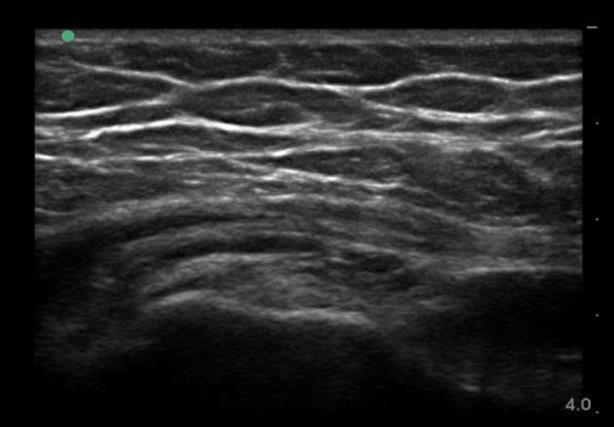

Bild: Laterale Hüfte, Trochanter anterior, Gelenkfläche 1